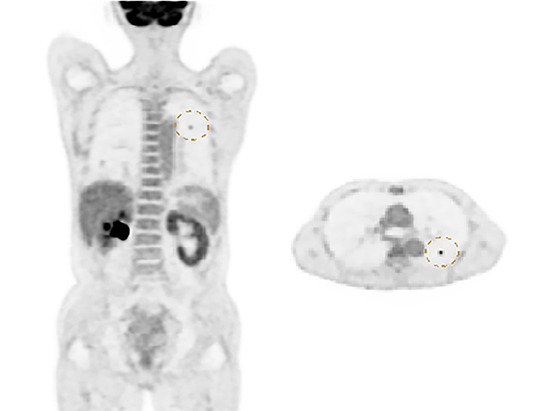

The large 24 cm axial digital PET field of view (FOV) provides exceptional image quality with 2.9 mm NEMA resolution that improves quantitative accuracy and small lesion detectability.